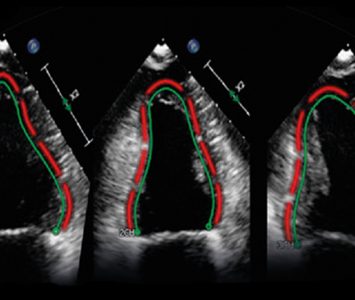

Médical : Philips acquiert l’allemand TomTec

TomTec est spécialisé dans les logiciels d’analyse de l’image. Il renforcera l’expertise de Philips en systèmes à ultrasons. (suite…)

TomTec est spécialisé dans les logiciels d’analyse de l’image. Il renforcera l’expertise de Philips en systèmes à ultrasons. (suite…)